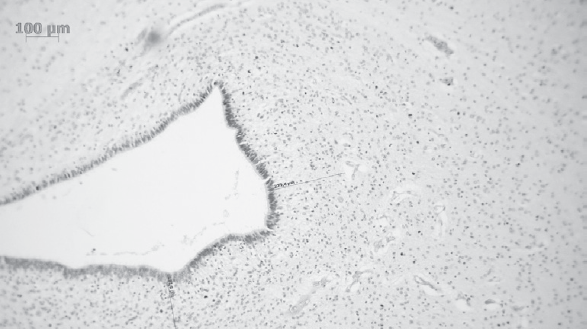

Результаты патоморфологического исследования ткани головного мозга в области герминального матрикса боковых желудочков. Толщину герминального матрикса измеряли в передних отделах боковых желудочков мозга. Толщина герминального матрикса изменялась обратно пропорционально ПКВ умерших детей (табл. 3, рис. 8, 9). Необходимо подчеркнуть, что у двоих умерших недоношенных новорожденных, ПКВ которых достиг 36 недель, при микроскопическом исследовании материала передних отделов боковых желудочков герминальный матрикс сохранялся.

Рис. 8. Тонкий слой герминального матрикса у ребенка, ПКВ 37–38 недель (окраска гематоксилином и эозином, ×100)

Fig. 8. A thin layer of the germinal matrix in a child, PCA 37-38 weeks (hematoxylin-eosin stain, ×100)

Рис. 9. Широкий слой герминального матрикса у ребенка, ПКВ 31–32 недели (окраска гематоксилином и эозином, ×100)

Fig. 9. A wide layer of the germinal matrix in a child, PCA 31-32 weeks (hematoxylin-eosin stain, ×100)

Результаты патоморфологического исследования показали регрессию герминального матрикса в боковых желудочках мозга с увеличением ПКВ, что соответствует данным других авторов [9, 10]. Субэпендимальный герминальный матрикс был наиболее выражен в передних отделах боковых желудочков. Отмечалась задержка полной редукции герминального матрикса у двух погибших детей, родившихся с ЭНМТ, в ПКВ 36 недель и старше, что может свидетельствовать о нарушении нейропластичности и задержки церебрального развития у этих новорожденных [10]. При физиологическом развитии головного мозга у недоношенных детей, достигших ПКВ 36 недель, герминальный матрикс при гистологическом исследовании не определяется [13].